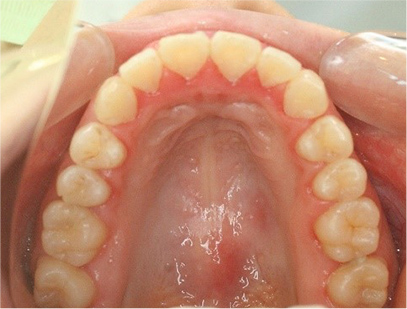

• 上側

• 下側

• 右側

• 左側